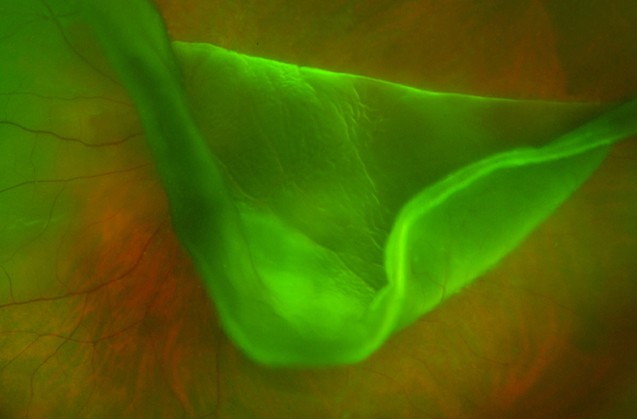

Para quem ainda não viu e desconhece o conteúdo da exposição “Visões”, explicamos que a mostra reúne um leque de fotografias reais, captadas no interior do olho humano, acabando por se revelar um instrumento de comunicação inovador entre Ciência e Arte.

De um total de três milhões de imagens, escolhemos 45 para a exposição que agora chega ao Luxemburgo. A vida que existe no interior do olho humano é revelada por estas imagens reais. São histórias de sucesso, escritas pelo traço cirúrgico deste grupo de especialistas que domina a arte de recuperar a vida que existe dentro dos nossos olhos.